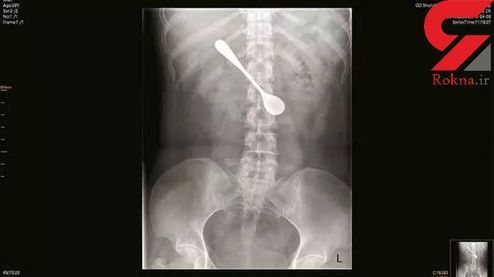

زن جوان قاشق ۱۳ سانتی را قورت داد +عکس

زنی که برای خلاص شدن از استخوان گیرکرده داخل گلویش قاشق قورت داد رسانهای شد.